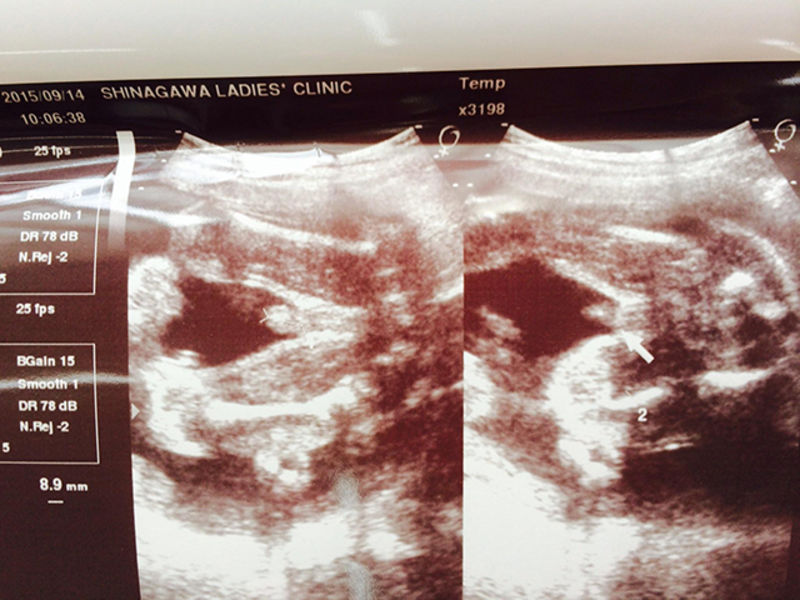

エコー写真 性別の見分け方 男の子女の子別エコー 妊娠週まとめてみました ママびよりウェブ

エコー写真 性別の見分け方 男の子女の子別エコー 妊娠週まとめてみました ママびよりウェブ

エコー写真 性別の見分け方 男の子女の子別エコー 妊娠週まとめてみました ママびよりウェブ

エコー写真 性別の見分け方 男の子女の子別エコー 妊娠週まとめてみました ママびよりウェブ

エコー写真 性別の見分け方 男の子女の子別エコー 妊娠週まとめてみました ママびよりウェブ

エコー写真 性別の見分け方 男の子女の子別エコー 妊娠週まとめてみました ママびよりウェブ

エコー写真 性別の見分け方 男の子女の子別エコー 妊娠週まとめてみました ママびよりウェブ

エコー写真 性別の見分け方 男の子女の子別エコー 妊娠週まとめてみました ママびよりウェブ

エコー写真 性別の見分け方 男の子女の子別エコー 妊娠週まとめてみました ママびよりウェブ